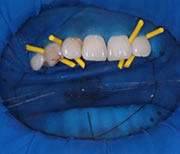

マイクロスコープと切っても切れないラバーダム防湿

お口の中には500種類以上の細菌が存在しています。

その数は、歯をよく磨いている人でも1,000億~2,000億、そのほとんどは唾液中に存在しています。

歯科治療では、いかに治療部位を唾液の細菌と湿気から遠ざけるかが長期的な治療の成功につながります。

このために、歯を唾液から簡単に隔離する手法がラバーダム防湿法です。治療中の薬液や器具の誤嚥を防ぐ患者様のためになる前処置です。